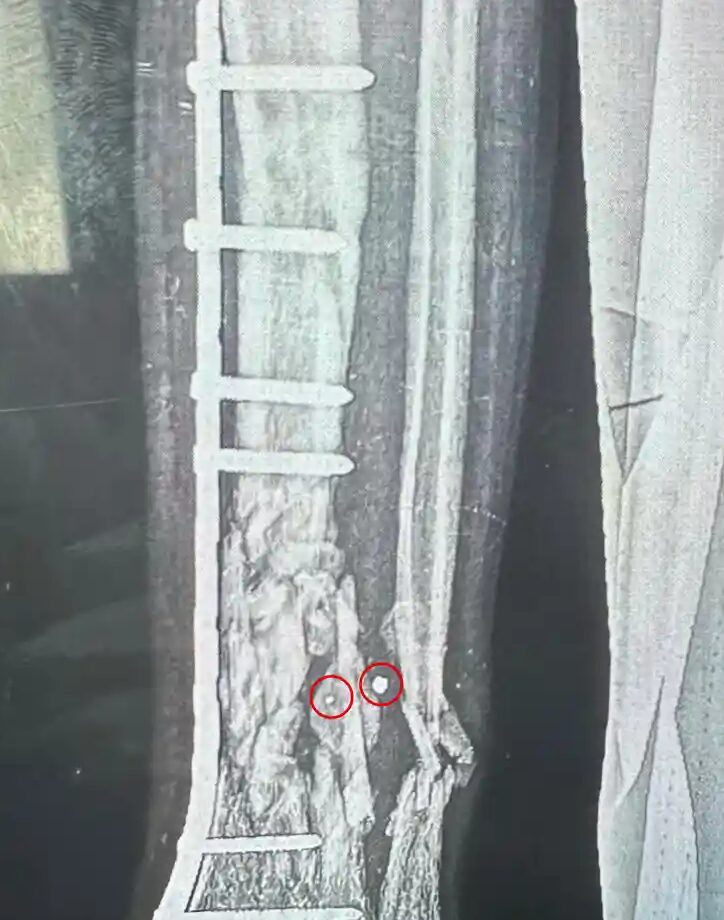

E difatti, le radiografie mostrate dai medici intervistati evidenziano “ossa distrutte, come fossero schiacciate da un camion, e una sola ferita piccola su un lato [il foro di ingresso]”. Questo avviene perché “le schegge di tungsteno viaggiano ad una velocità estremamente elevata, distruggendo facilmente tutti i tessuti molli e conficcandosi nelle varie parti dello scheletro”.

Le foto dei metalli rinvenuti, insieme alle descrizioni fornite dai medici, sono state analizzate da alcuni esperti di esplosivi. La conclusione che emerge è che “tali ferite sono provocate da bombe e proiettili dotati di una ‘camicia a frammentazione’ intorno alla testata esplosiva per massimizzare le vittime”. Trevor Ball, un ex tecnico esperto in esplosivi dell’esercito americano, ha spiegato il funzionamento delle armi impiegate dall’IDF, che “esplodendo, spruzzano cubi di tungsteno e sfere di metallo che sono molto più letali dell’esplosione stessa”.

Feroze Sidhwa, un chirurgo traumatologo della California, di ritorno dall’ospedale europeo nel sud di Gaza, ha dichiarato: “Circa la metà dei pazienti che ho curato erano bambini. Abbiamo visto molte ferite da schegge così piccole che talvolta sfuggivano al primo esame del paziente. Sono molto più piccole di qualsiasi altra cosa che abbia mai visto prima, ma causano enormi danni all’interno”. C’è poi un’altra testimonianza, che avvalora quanto appena riportato. Sanjay Adusumilli, un chirurgo australiano in servizio ad al-Aqsa, nel centro della Striscia, ha recuperato delle “schegge composte da minuscoli cubi di metallo di circa tre millimetri di larghezza durante un’operazione su un giovane ragazzo”. Ebbene, quelle schegge “distruggono ossa e organi lasciando solo un graffio sulla pelle”.